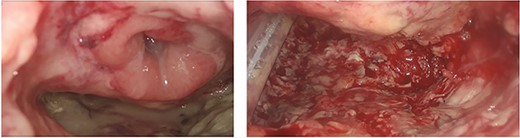

A 75-year-old Caucasian man was referred to our department on May 2022 because of a positive fecal occult blood test; subsequent colonoscopy showed an endoluminal substenosing lesion, located at sigmoid-rectal junction and extended distally for 5 cm. The tumoral bulk appeared centrally ulcerated and occupied more than three-fourth of the rectal circumference. The panel of biopsies resulted positive for well-differentiated adenocarcinoma. An angio-CT scan confirmed the presence of a sigmoid-rectal wall thickening, extended distally for about 6 cm, with significative narrowing of colonic lumen. Lateral spread appeared limited to the muscolaris propria, whereas the mesorectal component was unaffected; the presence of T2 lesion at preoperative diagnostic work-up was confirmed by MRI while neither hepatic nor pulmonary metastasis were detected. Tumor markers were within normal range. At physical examination, the patient appeared overweight (BMI 30.5), with no other significative comorbidity. Pre-operative staging led the Multidisciplinary Tumor Board to authorise a surgical approach. The patient underwent laparoscopic low anterior rectal resection with total mesorectal excision, with transanal end-to-end stapled colorectal anastomosis (7 cm from the anal verge) and ileostomy. Histological report of resected specimen confirmed the diagnosis of a G2 rectal adenocarcinoma, staged as pT3 pN1a R0, whereas the quality of mesorectal excision was graded as 3 (complete mesorectal fascia) according to Quirke classification. On the fifth post-operative day, the patient developed an increase in body temperature (37.8°C), in WBC count (10 × 103/uL) and in CRP plasmatic levels (6.63 mg/dL), as well as a corpuscular discharge from perianastomotic drainage; at physical examination, the patient showed a moderate tenderness on lower left abdomen with no clear signs of peritonitis. Early abdominal angio-CT scan showed a 15-mm discontinuity on the posterior wall of colorectal anastomosis, with perirectal fluid and extraluminal gas collection (Fig. 1). Low-flow endoscopic exploration confirmed the anastomotic wall defect in the right postero-lateral side, connected to a cavity filled with necrotic tissue (Fig. 2). Given the presence of ileostomy and perianastomotic surgical drainage and the absence of peritonitis signs with proper control of patient’s hemodinamics, we opted for a non-surgical treatment. On the sixth post-operative day, the patient underwent an Endo-SPONGE® device placement into the AL cavity, performed with TAMIS approach [7]. With the patient in lithotomy position, a GelPOINT® path transanal access platform was positioned; laparoscopic insufflation pressure was set at 10 mmHg. The right posterolateral anastomotic wall defect was visualised (Fig. 3), then the AL cavity was carefully measured (3 cm × 4 cm), washed with saline solution and explored up to the tip of surgical drainage. The polyurethane sponge was positioned under laparoscopic vision and then connected to the vacuum suction system, set at −40 mmHg. The Endo-SPONGE® device was replaced every 72 h for 2 weeks, then every 96 h for another 10 days; size and shape of the device were modified and gradually reduced according to the decreasing size of the cavity. Control CT scan and rectosigmoidoscopy confirmed the almost complete obliteration of the AL cavity. The Endo-SPONGE® device and the abdominal drainage were removed on the 25th post-operative day and the patient was then discharged without further complications. The patient has been addressed to adjuvant treatment protocol; a 3-month control CT scan showed neither distant metastases nor residual perirectal cavity. Once adjuvant treatment is completed, patient will be enrolled for colorectal anastomotic check and closure of ileostomy.

The visualisation of the right posterolateral dehiscence, the adjacent cavity (measuring 4 cm × 3 cm) with drainage by TAMIS approach.